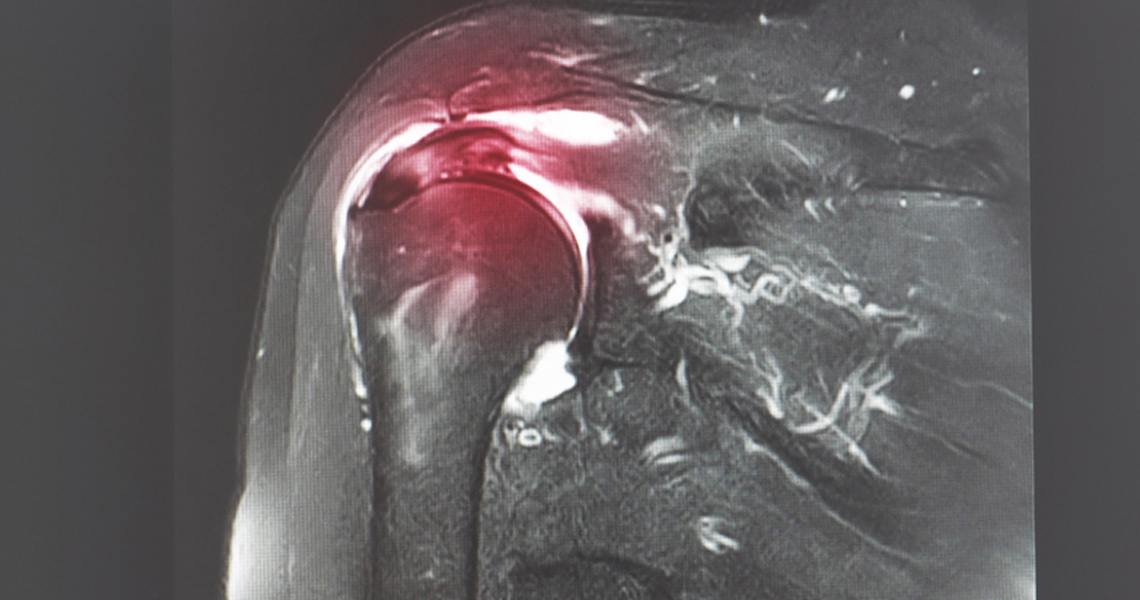

Shoulder arthroscopy is a minimally invasive surgical procedure that allows orthopaedic surgeons to visualise, diagnose, and treat a variety of shoulder conditions through small incisions using a specialised instrument called an arthroscope. This procedure is commonly performed to address issues such as rotator cuff tears, labral tears, shoulder impingement, shoulder instability, and shoulder arthritis. Shoulder arthroscopy offers several advantages over traditional open surgery, including smaller incisions, less tissue damage, faster recovery times, and reduced postoperative pain.

Rotator Cuff Tears: The rotator cuff is a group of muscles and tendons that surround the shoulder joint, providing stability and facilitating movement. Tears in the rotator cuff can occur due to injury, overuse, or degeneration, leading to pain, weakness, and limited mobility. Shoulder arthroscopy is often used to repair or reconstruct the torn rotator cuff tissue, restoring function and preventing further joint damage.

Labral Tears: The labrum is a cartilage structure that lines the rim of the shoulder socket, providing stability and cushioning to the joint. Tears in the labrum can occur due to trauma or repetitive shoulder movements, resulting in pain, clicking, or instability. Shoulder arthroscopy may be used to repair or debride the damaged labrum, improving joint stability and function.

Shoulder Impingement: Shoulder impingement occurs when the tendons of the rotator cuff become compressed or irritated as they pass through the subacromial space in the shoulder joint. This can lead to pain, inflammation, and restricted movement. Shoulder arthroscopy may be performed to remove inflamed tissue or bone spurs, relieving impingement symptoms and restoring shoulder function.

Shoulder Instability: Shoulder instability refers to excessive movement or dislocation of the shoulder joint, often resulting from ligament laxity or trauma. Shoulder arthroscopy may be used to tighten or repair the torn ligaments, restore stability to the joint, and prevent recurrent dislocations.

Preoperative Evaluation: Before undergoing shoulder arthroscopy, patients undergo a thorough evaluation, including physical examination, imaging studies (such as X-rays and MRI), and medical history review. This helps our orthopaedic surgeons determine the underlying cause of shoulder pain and develop a personalised treatment plan.

Surgical Procedure: During shoulder arthroscopy, our skilled surgeons use specialised instruments and an arthroscope to visualise the inside of the shoulder joint and perform minimally invasive surgical procedures. Depending on the specific condition, this may include rotator cuff repair, labral repair, subacromial decompression, or capsular tightening.